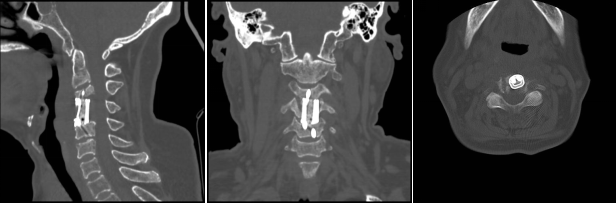

通訊員殷君發(fā)報道:近日,衡陽市中心醫(yī)院脊柱外科蘇光輝主任團(tuán)隊順利完成一例高難度頸椎骨質(zhì)破壞病灶切除+3D打印一體式椎體植入重建手術(shù),術(shù)后影像學(xué)顯示,植入內(nèi)植物位置滿意,與終板匹配性良好,穩(wěn)定性佳。術(shù)后患者生命體征平穩(wěn),癥狀明顯緩解,活動良好,目前已出院。此手術(shù)的圓滿成功是衡陽市中心醫(yī)院3D打印技術(shù)臨床應(yīng)用領(lǐng)域取得的又一重要突破,是湘南地區(qū)乃至全省首例疑難病癥的創(chuàng)新舉措,標(biāo)志著脊柱外科手術(shù)開始邁向個性化、精準(zhǔn)化。

術(shù)后影像學(xué)顯示,植入內(nèi)植物位置滿意,與終板匹配性良好,穩(wěn)定性佳。術(shù)后患者生命體征平穩(wěn),癥狀明顯緩解,活動良好,目前已出院。